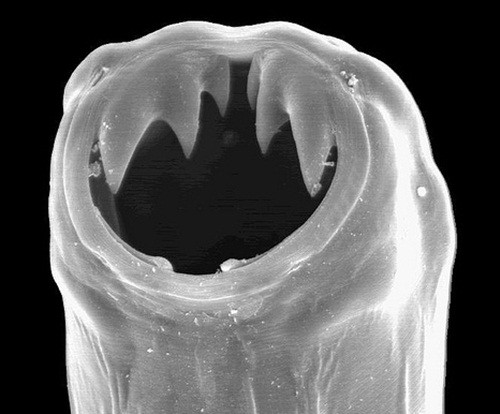

Giun móc có màu trắng sữa hoặc hơi hồng hoặc màu đỏ nâu tuỳ thuộc trong ruột giun có máu hay không, con đực dài khoảng 8-11mm, con cái dài 10-13mm. Trong bao miệng có 2 đôi răng hình móc bố trí cân đối ở bờ trên miệng, bờ dưới có các bao cứng giúp giun ngoạm chặt vào niêm mạc tá tràng để hút máu. Ngoài tác hại hút máu, chúng còn gây viêm hành tá tràng và tiết ra chất chống đông máu làm máu chảy rỉ trong ruột, chất độc ức chế cơ quan tạo máu sản sinh hồng cầu làm trầm trọng thêm tình trạng mất máu của bệnh nhân.